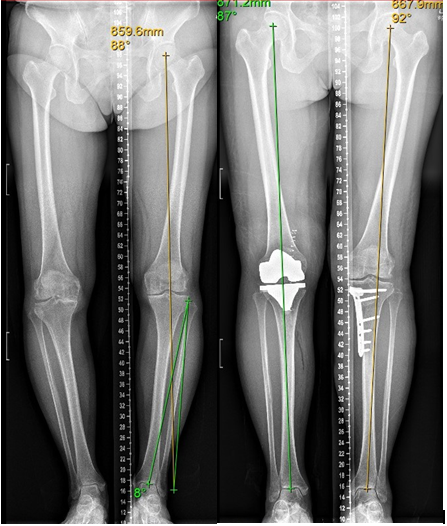

上图:患者左侧膝关节进行截骨术;右侧肢体进行膝关节置换手术,可明显看到术后患者下肢力线恢复正常。